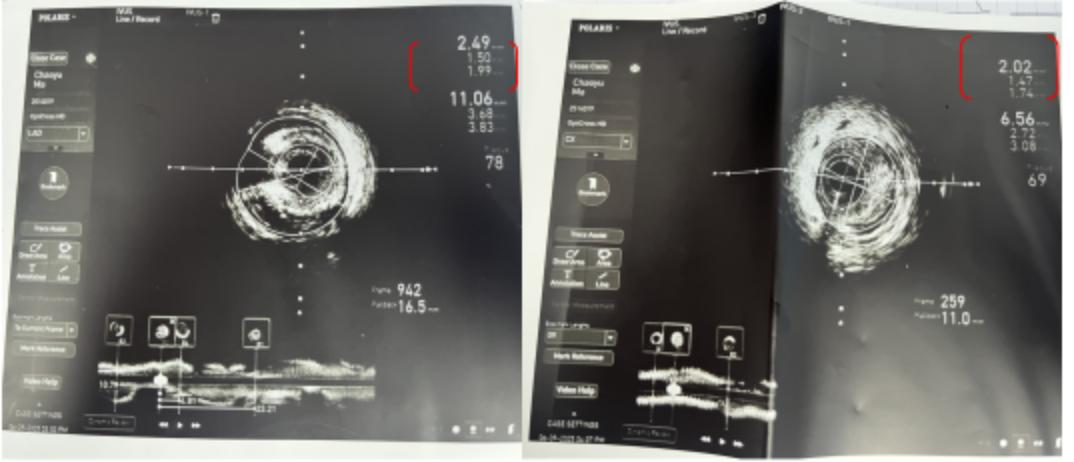

△IVUS检查

最终,在与家属沟通后,决定启用IVUS 技术。通过 IVUS 评估,医生精准锁定责任血管,在前降支植入支架,回旋支释放药物球囊,无需干预的右冠脉则采用强化药物治疗。

△IVUS实时指导手术

关键时刻,邓伟医师再次借助IVUS 技术,不到 1 小时就顺利完成左主干 PCI 术并修复原支架。